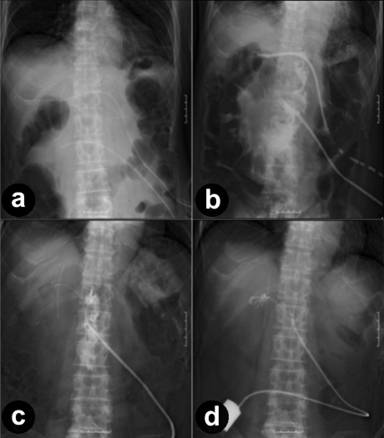

For pancreatic fluid drainage, 19Fr of Braked Drain™ (ETHICON, Inc., USA) (Figure 1a) was used; it was replaced with a Nelaton catheter™ (NIPRO Co., Ltd., Japan) one week or more after the operation (Figure 1b). The 19Fr drain was initially replaced with a 16Fr-diameter drain, and then the diameter of the drain was gradually narrowed to 10Fr. In many cases, the postoperative volume of fluid drainage decreases gradually and drain removal will become possible. However, for our six cases drain removal was difficult due to persistent drainage of pancreatic fluid, and fistula closing was performed using tissue adhesive.

Figure 1. a. When the operation was finished, 19Fr of Braked Drain (ETHICON, Inc.USA) was placed on the upper and lower sides of pancreaticoduodenectomy portion. b. These were replaced with a Nelaton catheter™ (NIPRO Co., Ltd., Japan) one week or more after the operation. c. The fistula closing cannot be carried out whilst the cavity surrounding the pancreaticojejunostomy portion remains. d. The fistula closing was performed at the time that the cavity disappeared and the fistula straightened. |

The six cases who underwent the treatment had remained in hospital for an average of 54.2±32.9 days post-pancreaticoduodenectomy until the fistulae were closed using this tissue adhesive method. The fistula closing could not be carried out whilst the cavity surrounding the pancreaticojejunostomy remained (Figure 1c). We injected fibrin glue from the drain which we narrowed to 10Fr, when the cavity had disappeared, and the fistula had been straightened (Figure 1d). Then the fistula closing could only be performed.